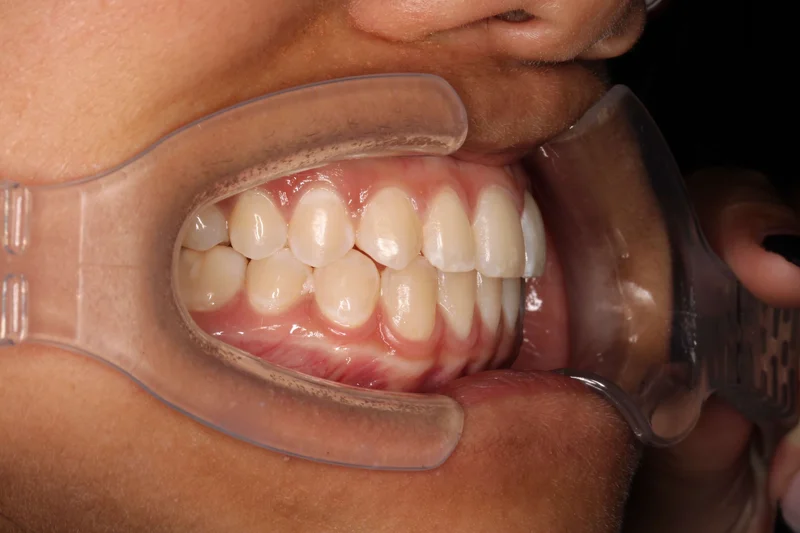

This Las Vegas teen patient came in with crowding and a crossbite of her upper right canine. She was also congenitally missing her upper left canine, so Dr. Benson treated her with the baby tooth still in place. When orthodontic treatment was finished, a crown was placed on the baby tooth. Dr. Benson treated her with Clear/Ceramic braces, and she completed her treatment in 17 months.

Right Buccal

Right Buccal - After Treatment

After